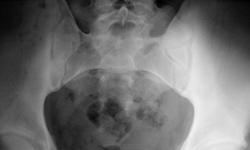

17-летний юноша пришёл на обследование правого ТБС. Стали беспокоить боли. Точный анамнез к сожалению передать не смогу, т.к. меня не было. Назначил дообследование. Ваше мнение уважаемые коллеги?

Болезни Бехтерева я не вижу, но не могу понять почему левая подвздошная кость выглядит такой склерозированной. Как это выглядит на оригинальном снимке - тоже склероз? или это такой эффект от фотоаппарата?!

На мой взгляд, при производстве рентгенограммы, центрация была не "в ту степь"...

Я с вами согласна, Валентин Львович. Тазобедренные суставы не вызывают беспокойства. Я бы рекомендовала пациенту дообследовать поясничный отдел позвоночника. Игорь Артурович, какое дообследование вы порекомендовали данному пациенту?

прицельно снять крестцово-подвздошные сочленения и доснимем поясницу. Эффекта от фотоаппарата здесь нет, видно прав Валентин Львович о нарушении центрации. У нас с этой центрацией есть проблемы. Обещают сделать.

Интересный материальчик я нашел в "буржуинском лучевом сообществе", материальчик на основании исследований - МРТ. Так вот, тот материальчик свительствует, что первичные признаки (начальные) нужно искать в телах позвонков (поясничные), а не в крестцово-подвздошном сочленении..., удивился, но доказано основательно...

Переходной пояснично-крестцовый позвонок. Что-бы поставить все точки над і - рентгенограммы п/кр. отдела в 2-х пр. на 20х40.

Так называемый "пяточный эффект".